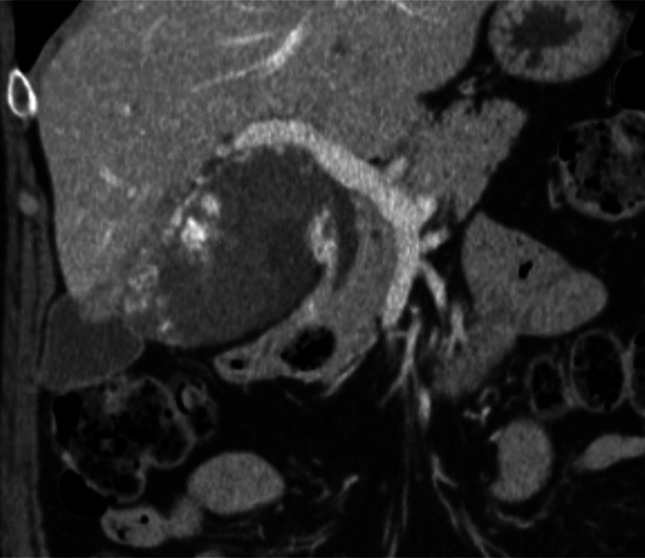

Symptomatic hepatic hemangiomas are commonly treated by transcatheter arterial embolization as an alternative to surgical resection. Bile duct complications are rare. An 80-year-old woman had a progressive refractory stricture postbleomycin transcatheter arterial chemoembolization. Magnetic resonance cholangiopancreatography showed that the hemangioma reduced in size, but there was a new 2 cm hilar stricture on cholangiopancreatography. Digital cholangioscopy and biopsy showed benign changes. Despite repeat dilations and stent treatments, she had persistent stricture and recurrent cholangitis. The stricture was not operable. The stricture was likely from angiosclerotic effects of bleomycin. The bile duct is prone to ischemic injury as it lacks dual blood supply.